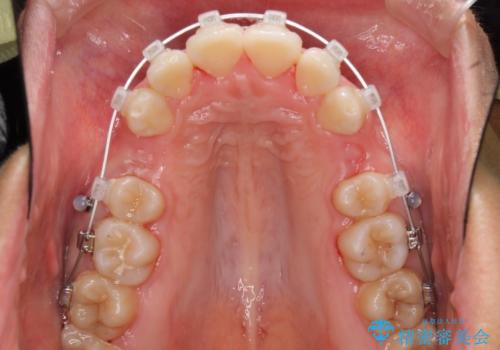

- クリアブラケット

口元を積極的に引っ込めるために、上下左右の第一小臼歯を4本抜歯することとしました。

途中で来院されない時期があったため、期間が長引き、更には磨き残しが多かったことで虫歯が多く発現してしまいました。

しっかりと通院するようになってからは順調に治療が進み、横顔の印象が変わるほどスッキリとした口元となりました。